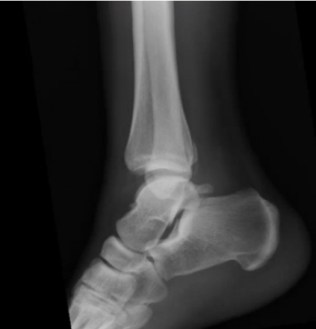

What’s the diagnosis? Gepost op 10 januari 2019 door netwerkvsseh What’s the diagnosis? @emdaily.cooperhealth.org Dit delen: Delen op X (Opent in een nieuw venster) X Share op Facebook (Opent in een nieuw venster) Facebook Delen op LinkedIn (Opent in een nieuw venster) LinkedIn E-mail een link naar een vriend (Opent in een nieuw venster) E-mail Afdrukken (Opent in een nieuw venster) Print Vind-ik-leuk Aan het laden... Gerelateerd